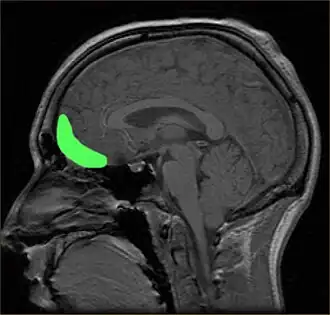

Prefrontal cortex

The prefrontal cortex is previously known for its roles in the perception of colored objects, decision making, and memory. Recent studies have also linked it to the conscious aesthetic experience because it is activated during aesthetic tasks such as determining the appeal of a visual stimuli. This may be because a judgment is needed, requiring visiospatial memory. In a study performed by Zeki and Kawabata, it was found that the medial orbito-frontal cortex (mOFC) is involved in the judgment of whether a painting is beautiful or not.[44] There is high activation in this region when a person views paintings which they consider beautiful. Other evidence shows that this same area is active during the experience of beauty derived from different sources,[55] including musical beauty[56] and moral beauty,[57] and even mathematical beauty.[58] Experience of the sublime, as opposed to the beautiful, results in a different pattern of brain activity;[59] moreover, where it comes to judgment, although aesthetic and perceptual judgments leads t activity in the same brain areas, the pattern of activity is also different between the two, one of the most marked differences being the involvement of mOFC in aesthetic, but not in perceptual, judgments.[60] Surprisingly, when a person views a painting which they consider ugly, no separate structures are activated. Therefore, it is proposed that changes in the intensity of activation in the orbito-frontal cortex correlate with the determination of beauty (higher activation) or ugliness (lower activation).

Conversely, activity in the motor cortex showed the opposite pattern.[61] Additionally, the medial OFC has been found to respond aesthetics in terms of the context of which it is presented, such as text or other descriptions about the artwork. The current evidence linking the OFC to attributed hedonistic values across gustatory, olfactory, and visual modalities, suggests that the OFC is a common center for the assessment of a stimulus's value.[47] The perception of aesthetics for these areas must be due to the activation of the brain's reward system with a certain intensity.

Additionally, the prefrontal dorsalateral cortex (PDC) is selectively activated only by stimuli considered beautiful whereas prefrontal activity as a whole is activated during the judgment of both pleasing and unpleasing stimuli.[8] The prefrontal cortex may be generally activated for directing the attention of the cognitive and perceptual mechanisms towards aesthetic perception in viewers untrained in visual arts.[23] In other words, related directly to a person viewing art from an aesthetic perception due to the top-down control of their cognition. The lateral prefrontal cortex is shown to be linked to higher order self-referential procession and the evaluation of internally generated information. The left lateral PFC, Brodmann area 10, may be involved in maintaining attention on the execution of internally generated goals associated with approaching art from an aesthetic orientation.[23]